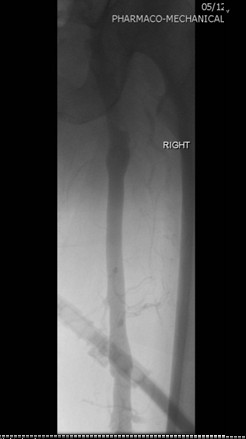

Venografía de la vena femoral tras trombectomía fármaco-mecánica (PMT) mediante la técnica Power Pulse Delivery (se usaron 15 ml de una solución de 50 mg de tPA  en 500 ml de solución salina natural) seguida por 2 pasadas con el catéter DVX de AngioJet.

Venografía en posición decúbito supino tras introducir 2 veces el catéter DVX de AngioJet. Vena ilíaca externa y vena femoral común del paciente. Estenosis severa de la vena ilíaca común.